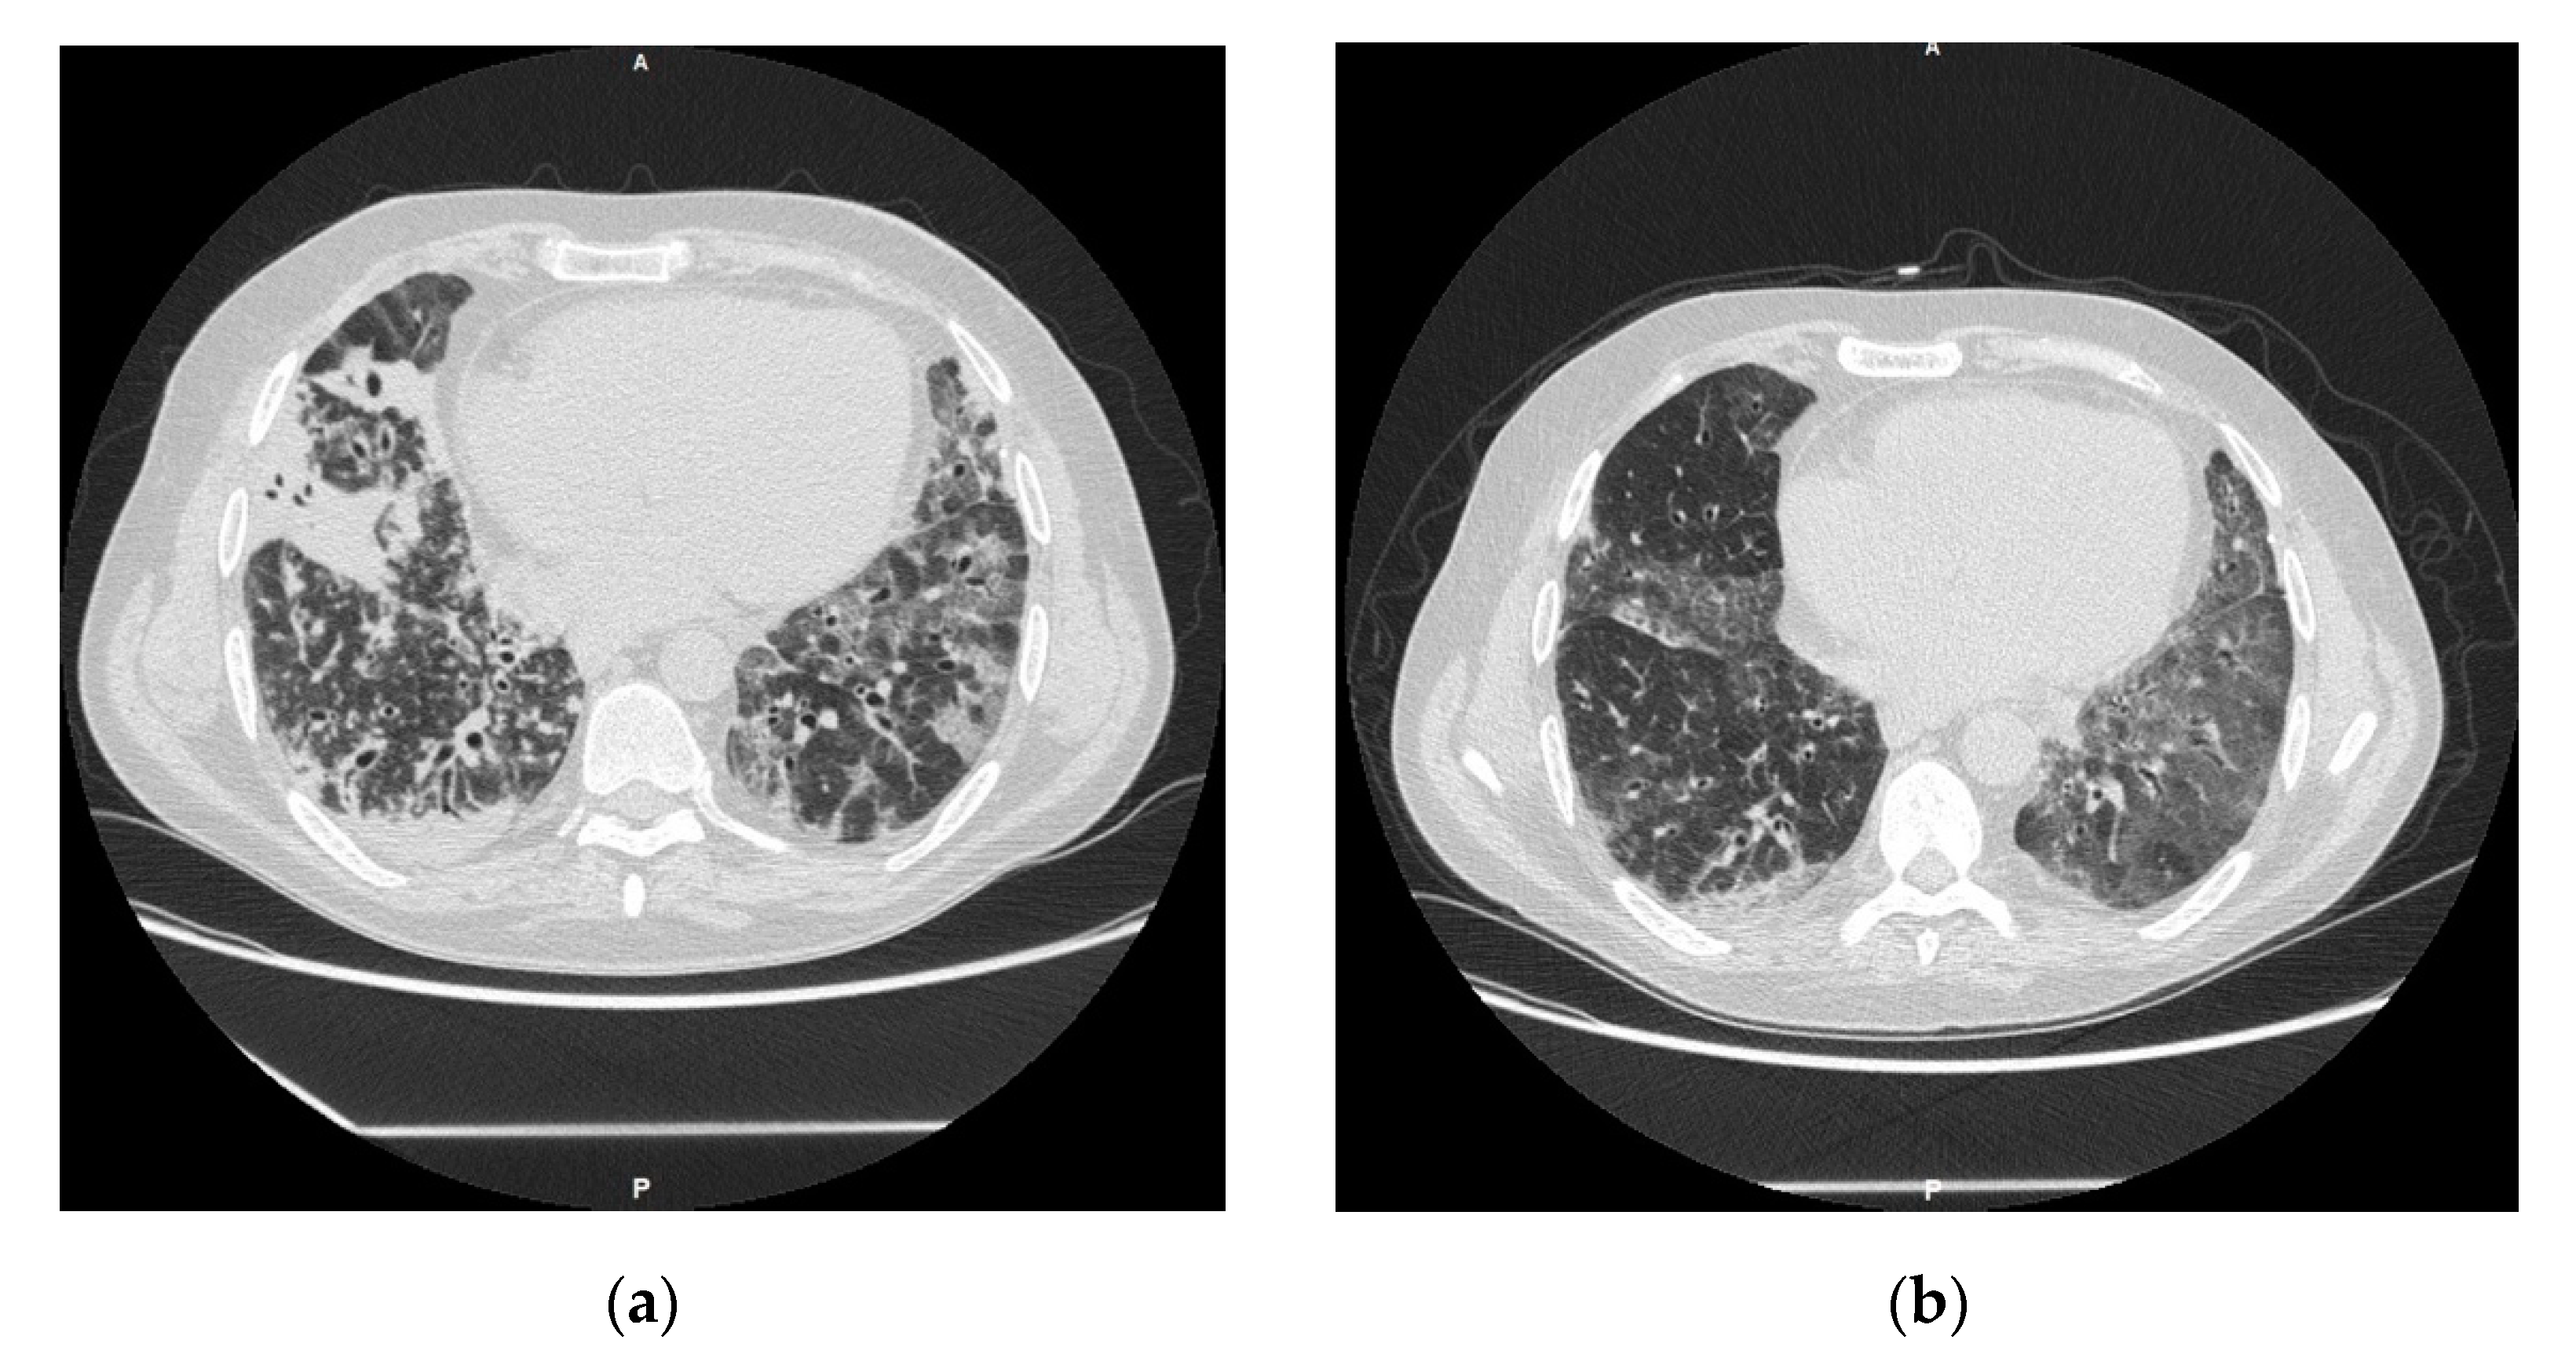

2.1. Case 1

2.2. Case 2